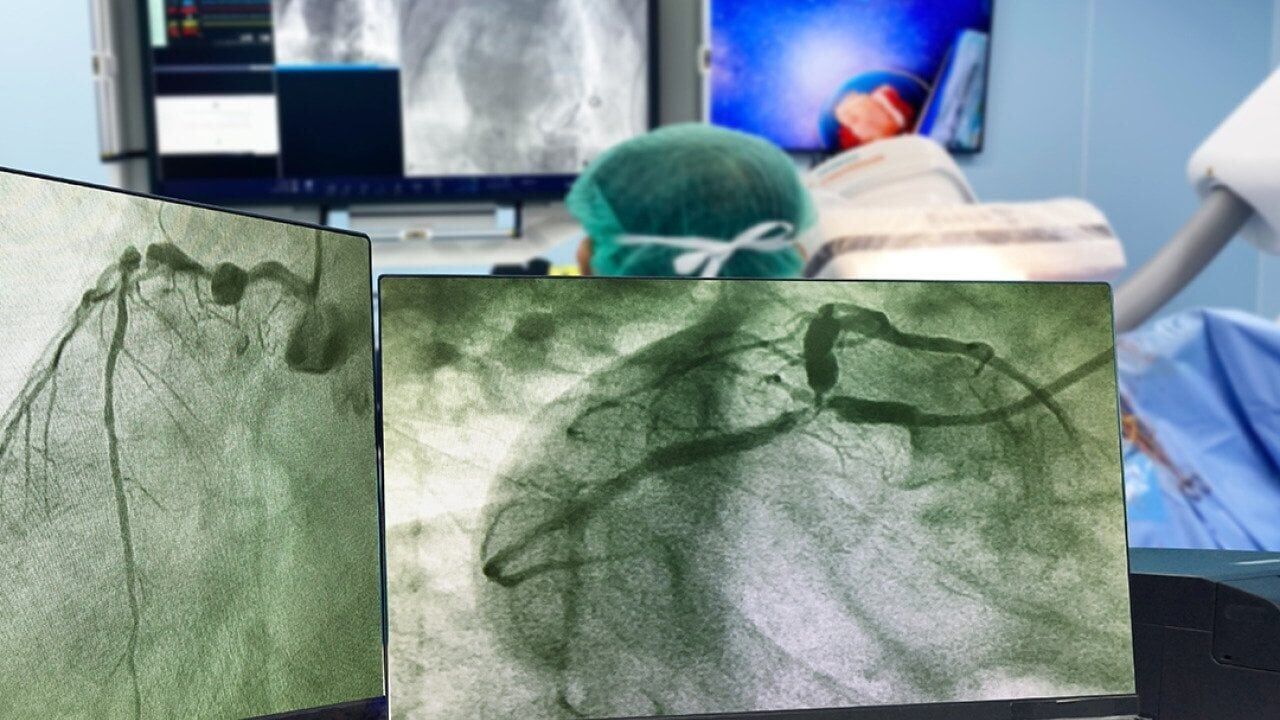

Northwell Health reports on the importance of heart checkups, highlighting tests like EKGs and angiograms that can identify heart risks.

A new study by Dutch scientists shows that AI can "reliably" take over the analysis and rapidly assess arteries for weak spots.